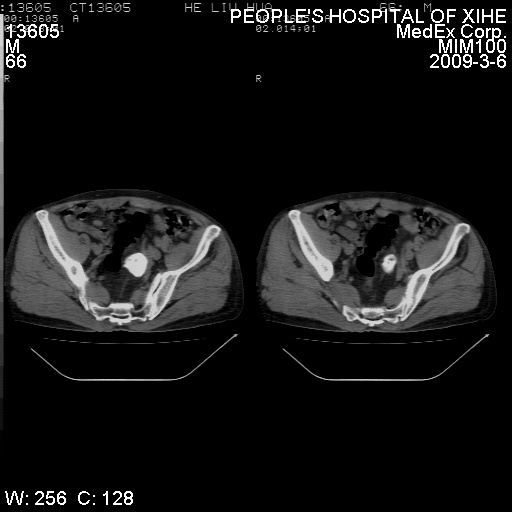

标题: CT18522:男,66岁。考虑结核有错吗 [打印本页]

标题: CT18522:男,66岁。考虑结核有错吗

x线片示:骶骨密度增高。

考虑----腰椎骶化-----退变-----椎管狭窄

腰骶椎退行性改变。

腰骶椎退行性改变,建议重建看看!

退行性变,椎体滑脱

腰椎滑脱并有退变

退行性变,椎体滑脱。建议同椎体平行进一步扫描。